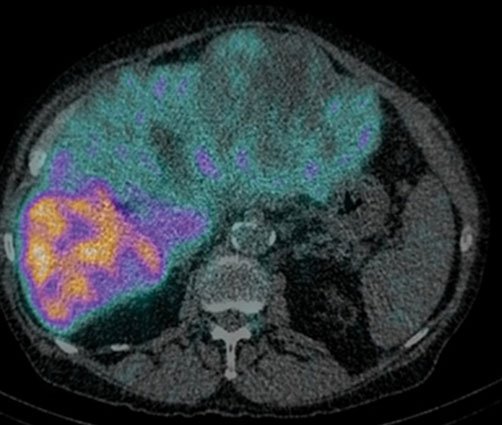

Radioembolization is a minimally invasive procedure that combines embolization and radiation therapy to treat liver cancer. Tiny glass or resin beads filled with the radioactive isotope yttrium Y-90 are placed inside the blood vessels that feed a tumor. This blocks the supply of blood to the cancer cells and delivers a high dose of radiation to the tumor while sparing normal tissue. It can help extend the lives of patients with inoperable tumors and improve their quality of life.

The radiation from yttrium-90 continually decreases over a two-week period and disappears after 30 days. The tiny microspheres remain in the liver without causing any problems.

STEP 1: Assessment of lung shunt fraction

STEP 2: Radioembolization after 7-10 days